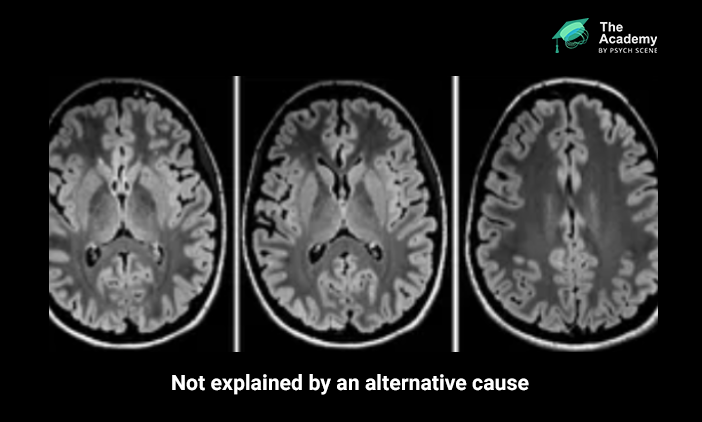

- MRI features suggestive of encephalitis

Supportive MRI findings may include T2-FLAIR hyperintensity in the medial temporal lobes or in multifocal grey or white matter areas compatible with inflammation.